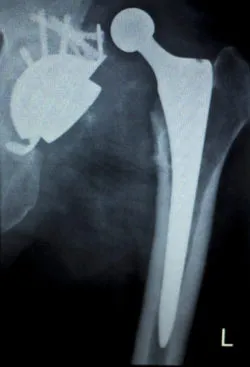

metal hip replacement xrayThe Stryker Rejuvenate hip replacement device is one of a number of hip replacement models that has been linked to problems resulting from its metal-on-metal design.

The Stryker Rejuvenate hip replacement and other metal hip implants that lead to serious problems are designed in a way that allows metal parts of the hip implant to touch during normal activities.

In the metal-on-metal hip implant design like that of the Stryker Rejuvenate hip replacement, when the metal parts interact during movement, metal particles flake off and enter surrounding tissue as well as the bloodstream of the patient.